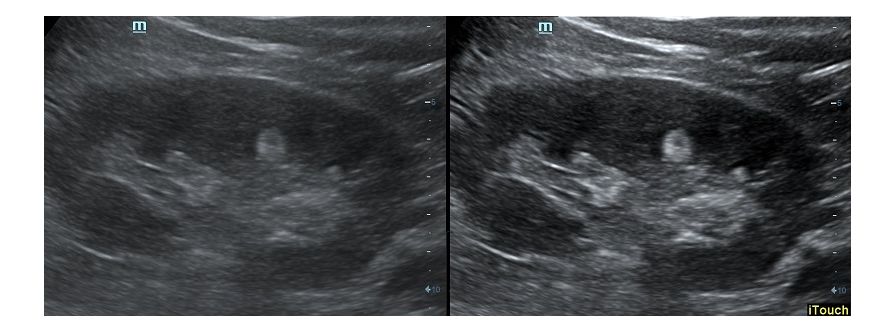

Обзор функции УЗИ: iTouch - автоматическая оптимизация изображения

Оптимизация изображения происходит и за счет постобработки. Наиболее часто используемый инструмент - общее усиление (Gain). Усиление делает изображение «ярче», но чем сильнее усиление, тем меньше различия между структурами. Также используются усиление по времени (TGC) и усиление по длине (LGC), которые позволяют изменять отображение на экране послойно, позволяя подсветить гипоэхогенные участки, или, наоборот, снизить визуально эхогенность слишком ярких моментов. Данный вид оптимизации требует много времени, для упрощения работы доктора на приборах Mindray внедрена система автоматической оптимизации - iTouch.